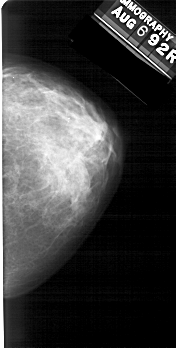

A_1391_1.LEFT_MLO

LEFT_MLO LINES 5236 PIXELS_PER_LINE 3076 BITS_PER_PIXEL 12 RESOLUTION 43.5 OVERLAY